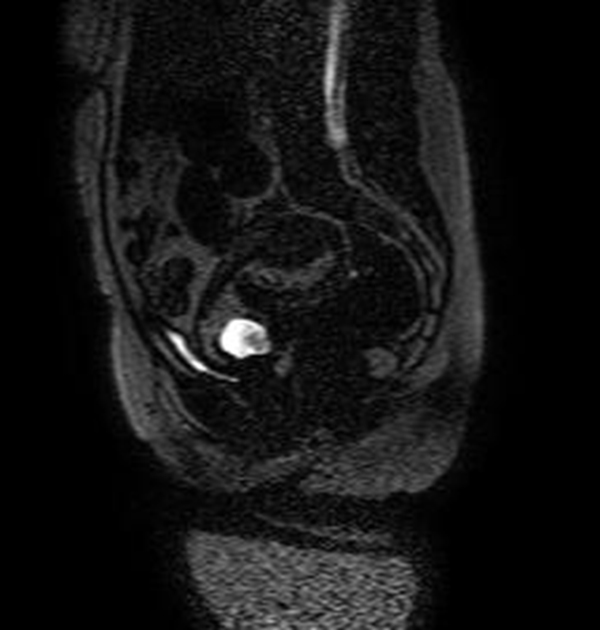

Se realizó una RNM (Philips 1.5 Tesla) que permitió confirmar el diagnóstico de EEC (figuras 5 a 8).

Figura 6 Imagen sagital de RMN en T2 con supresión grasa (SPIR) que muestra el saco gestacional limitado anteriormente por una banda de señal intermedia correspondiente a la reacción decidual y rodeada a su vez por el miometrio hipointenso

Figura 7A Imágenes de RMN potenciadas en T2 con supresión de la grasa. A) Plano axial y B) Plano coronal, donde se identifica el saco gestacional como una estructura quística con tejido fetoplacentario en su interior y localizado en el canal cervical

Figura 7B Imágenes de RMN potenciadas en T2 con supresión de la grasa. A) Plano axial y B) Plano coronal, donde se identifica el saco gestacional como una estructura quística con tejido fetoplacentario en su interior y localizado en el canal cervical